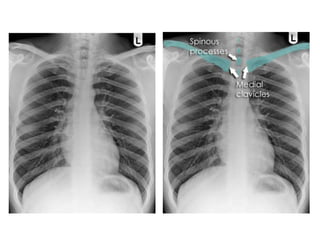

c. Centering & Rotation

 Can be assessed by observing the clavicular

heads and determining whether they are equal

distance from the spinous process of the thoracic

vertebral bodies.

 Good centering: 1/3 of heart is to right & 2/3 to

left of midline.